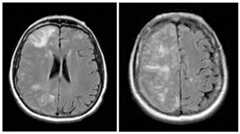

Figure 1.

ARIA-E as seen on FLAIR images from a monoclonal antibody trial demonstrating increased MR signal in multiple regions of the right hemisphere affecting both gray and white matter.

ARIA-E most commonly manifests as increased MR signal intensity on FLAIR or other T2-weighted sequences in the parenchyma and/or leptomeninges in the parietal, occipital, and frontal lobes, but has also been observed in the cerebellum and brainstem [3]. It is not yet clear whether the edema begins in grey matter in some cases, as associated gyral swelling is sometimes apparent, with edema tracking into the underlying white matter, or whether there may be separate processes that affect grey and white matter. The parenchymal signal abnormalities can be quite subtle in a single region, multi-focal, or nearly pan-hemispheric (seeFigure 1 below).